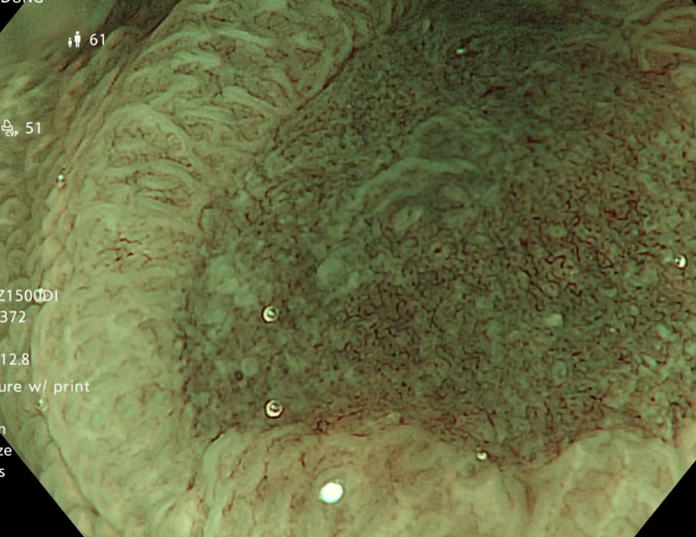

Kết quả nội soi đại tràng: có 3 polyp đại tràng (Paris Is, Kudo IIIL) (đã được cắt polyp qua nội soi), đại tràng sigmoid đã cắt một phần, tổn thương lồi đại trực tràng dạng polyp không cuống, ranh giới rõ, bề mặt màu hồng, có nhiều polyp có lớp nhầy ở trên bề mặt và thấy có hình ảnh da gà xung quanh tổn thương. Trên hình ảnh M-NBI thấy các tổn thương có các tuyến giãn nhẹ nhưng còn đều, mạch máu giãn nhẹ, chưa có biến đổi hình dạng --> đã tiến hành sinh thiết

Hình 2: Hình ảnh nội soi đại tràng

Tổn thương trên nội soi là hình ảnh các tổn thương lồi tại đại trực tràng dạng polyp không cuống, ranh giới rõ, bề mặt màu hồng, có nhiều polyp có lớp nhầy ở trên bề mặt. Chúng tôi nghĩ đến đây là hình ảnh của đa polyp mũ đại tràng mặc dù kết quả mô bệnh học chỉ kết luận là tổn thương viêm trợt mạn tính đang hoạt động, tạo hình ảnh giả polyp. Do trước đó cô ấy đã trải qua nhiều phương pháp điều trị theo hướng viêm ruột như kháng sinh Tinidazol, Levofloxacin, mesalazine… nhưng tình trạng đại tiện nhiều lần không được cải thiện, cùng với đó chúng tôi ghi nhận thấy có sự hiện diện của vi khuẩn H.pylori ở dạ dày. Vì vậy chúng tôi đã quyết định điều trị diệt trừ vi khuẩn H.pylori bằng phác đồ 4 thuốc: Tetracyclin 2g/ngày, Tinidazol 1,5g/ngày, Esomeprazol 80 mg/ngày, Bismuth 480 mg/ngày, thời gian điều trị là 2 tuần.